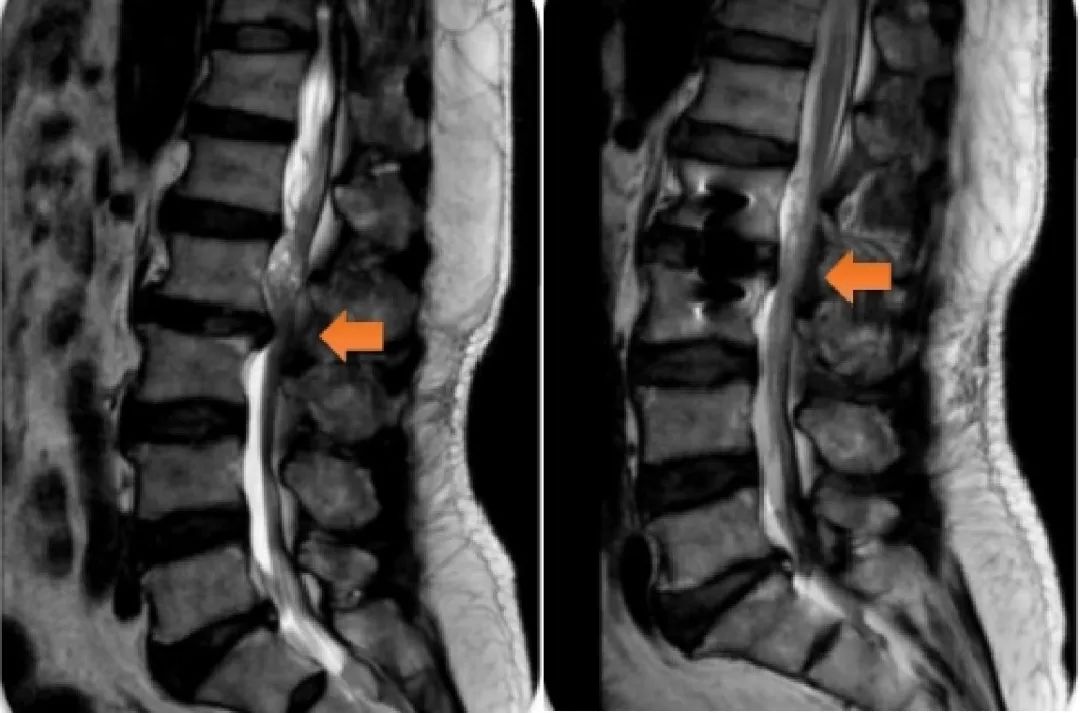

患者手术前后影像检查图,橙色箭头为颈椎狭窄处